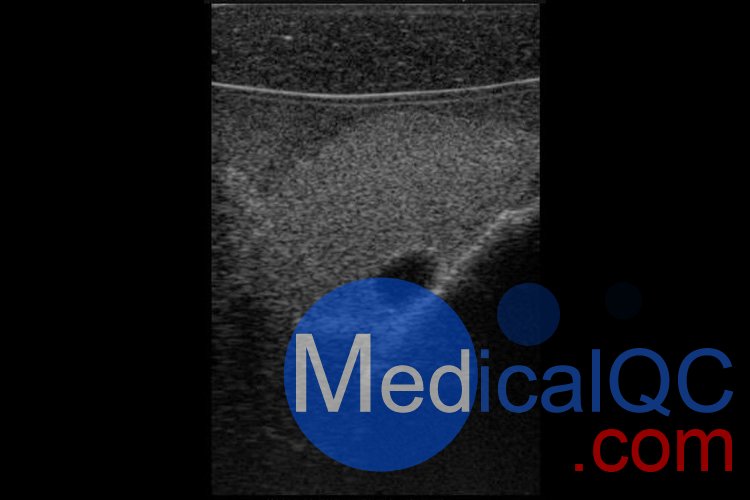

Cirs074甲狀腺超聲訓練模體,Cirs074甲狀腺穿刺模體超聲成像圖:

Cirs074甲狀腺超聲訓練模體,Cirs074甲狀腺穿刺模體超聲成像圖